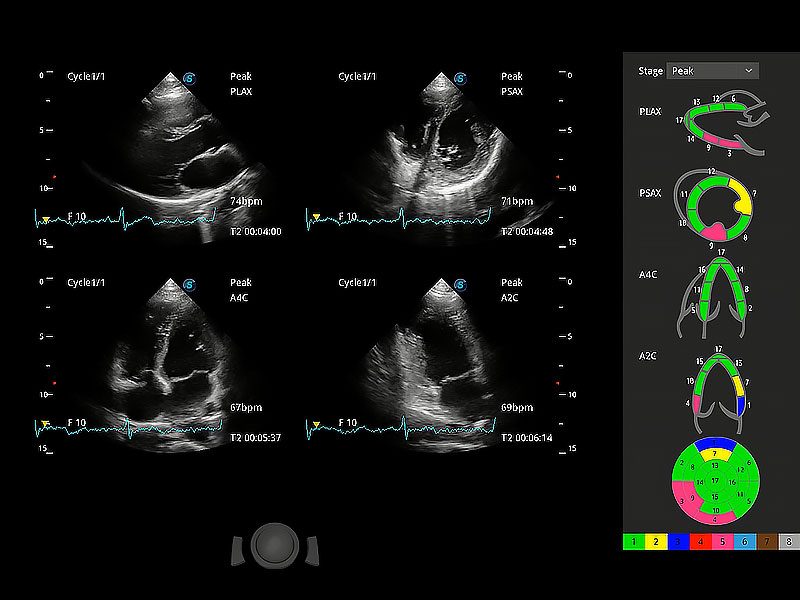

通过心肌识别技术与二维斑点追踪技术相结合,对心脏的超声图像进行量化分析。计算心肌17个节段的应变、应变率、速度、位移等,并通过牛眼图的形式进行呈现。

具备多种协议可选,同时支持17阶段划分法和专业的SE报告。

能够基于左心室壁追踪和辛普森法,自动计算射血分数,支持多个可移动点描迹,与手动测量相比,极大节省了动物医生的时间和精力。